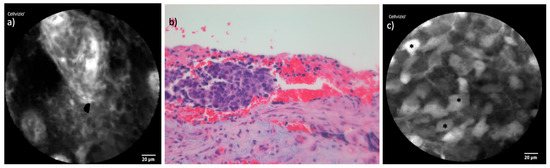

3.6. Sinonasal Malignant Melanoma

In the endoscopic inspection, both cases of SNMM displayed light pigmentation, which initially suggested SNMM as a potential diagnosis. CLE examination of the tumors revealed small, spherical cells, a finding that corresponded well with the histological images. However, while the histopathological analysis identified melanin pigments within the tumor tissue, these pigments were not detectable using CLE. Figure 9 shows the comparison of exemplary CLE and histopathological images of SNMM.

Figure 9. Comparison of CLE and histopathological cross-section in SNMM: (a) CLE image of one of the included SNMM with small round cells and a cross-section of a capillary (*). (b) Corresponding histopathological cross-section H&E staining showing the highly similar round cellular shape. The brown melanin pigment is not detected in the CLE image.

4.2.5. Sinonasal Malignant Melanoma

SNMM is a rare and aggressive tumor that is often diagnosed at an advanced stage due to its nonspecific symptoms and challenging localization. This malignancy is associated with a high rate of recurrence, exceeding 50%, and a poor prognosis, with a 5-year survival rate of less than 25% [33]. In a preliminary report, our group previously evaluated the applicability and potential advantages of CLE in diagnosing SNMM, highlighting its ability to provide real-time imaging and facilitate surgical decision-making during resection [34].

In the current study, CLE successfully visualized small, spherical tumor cells within the SNMM cases, corresponding well to the histopathological findings. While CLE is not expected to highlight melanin pigments due to their lack of vascularization, we frequently observed a generally darker overall appearance in the CLE images of SNMM tumors compared to other entities, as shown in Figure 9. This raises the question of whether the darker imaging may be indirectly influenced by the presence of melanin pigments within the tumor tissue.